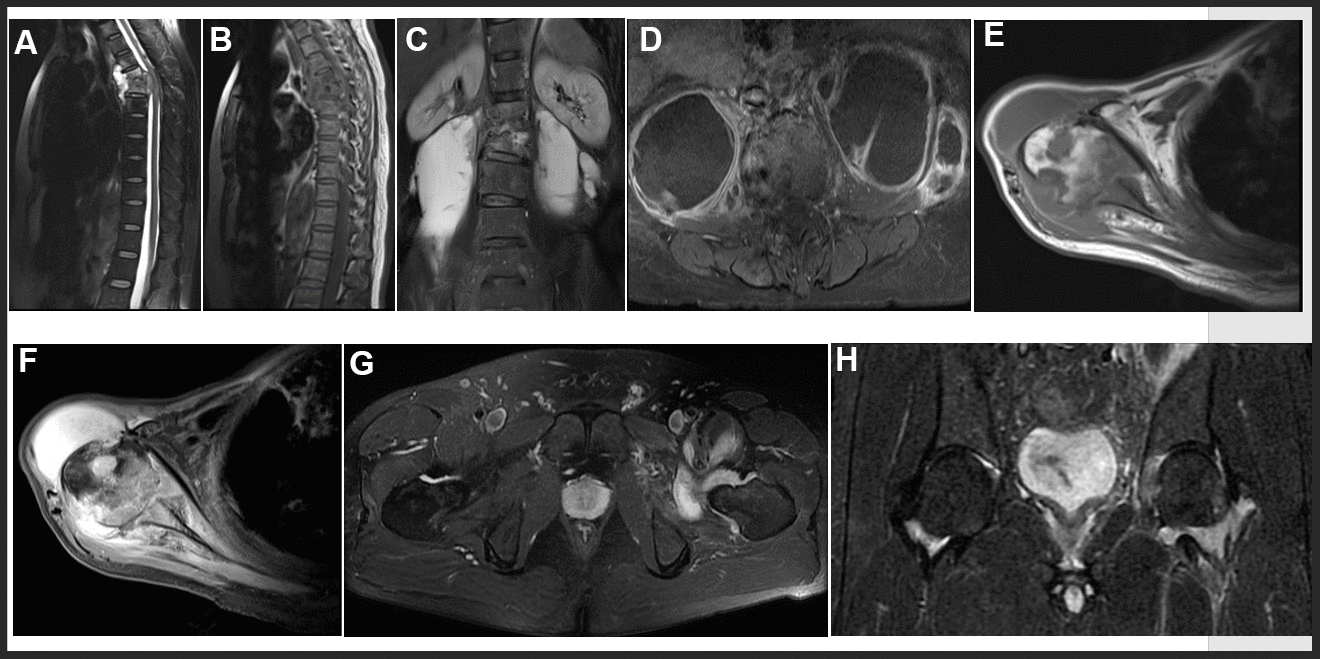

Figure 3. Representative examples of MRI in OTB patients. (A, B) Thoracic spine tuberculosis: showing destruction of vertebral and paravertebral abscess. (C, D) Lumbar spine tuberculosis: showing destruction of vertebral and psoas abscess. (E, F) Right shoulder tuberculosis: showing worm like destruction of the right humeral head with effusion in the articular cavity. (G, H) Left hip joint tuberculosis: showing left hip joint synovitis and synovial fluid.